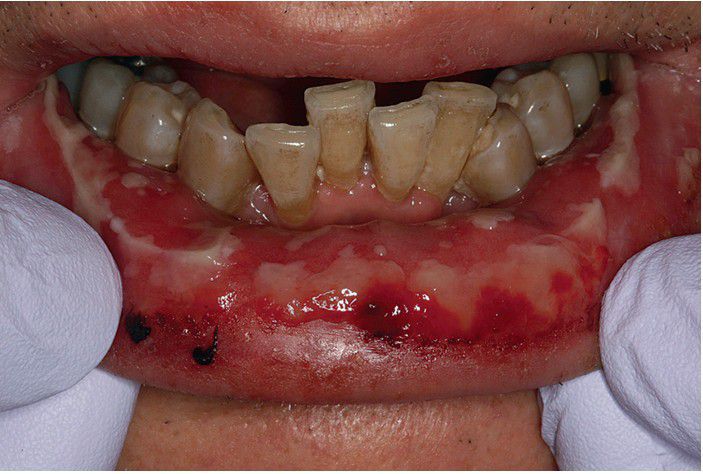

Erythema Multiforme.

Focal hemorrhagic crusting of the lips is seen in conjunction with diffuse shallow ulcerations and erosions involving this patient’s mandibular labial mucosa.